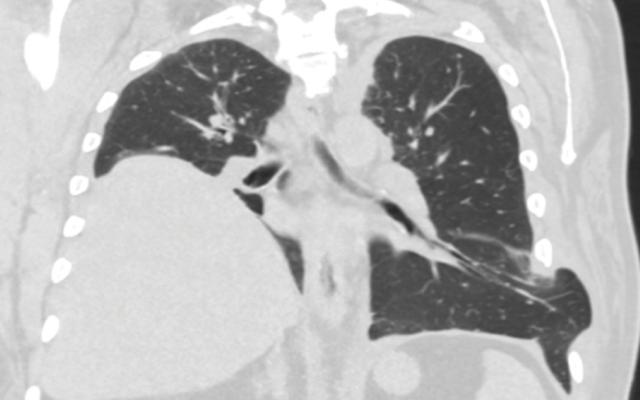

Een 79-jarige vrouw kwam op de SEH vanwege pijn en een zwelling in de buik. De zwelling was plotseling ontstaan na een eenmalige hoestbui. De patiënte was bekend met angina pectoris, waarvoor zij onder andere acetylsalicylzuur gebruikte. Bij lichamelijk onderzoek was de patiënte tachycard en hypotensief (hartfrequentie: 112 slagen/min; bloeddruk: 79/59 mmHg). Wij zagen een zwelling van de linker buikhelft en een groot subcutaan hematoom in de linker flank (figuur a). Bloedonderzoek liet een anemie zien. De hemoglobineconcentratie was 6,5 mmol/l (referentiewaarde: 7,5-10); 10 dagen eerder was die nog 7,5 mmol/l. De serumlactaatconcentratie was verhoogd (8,1 mmol/l; referentiewaarde: 0,5-2,2)…